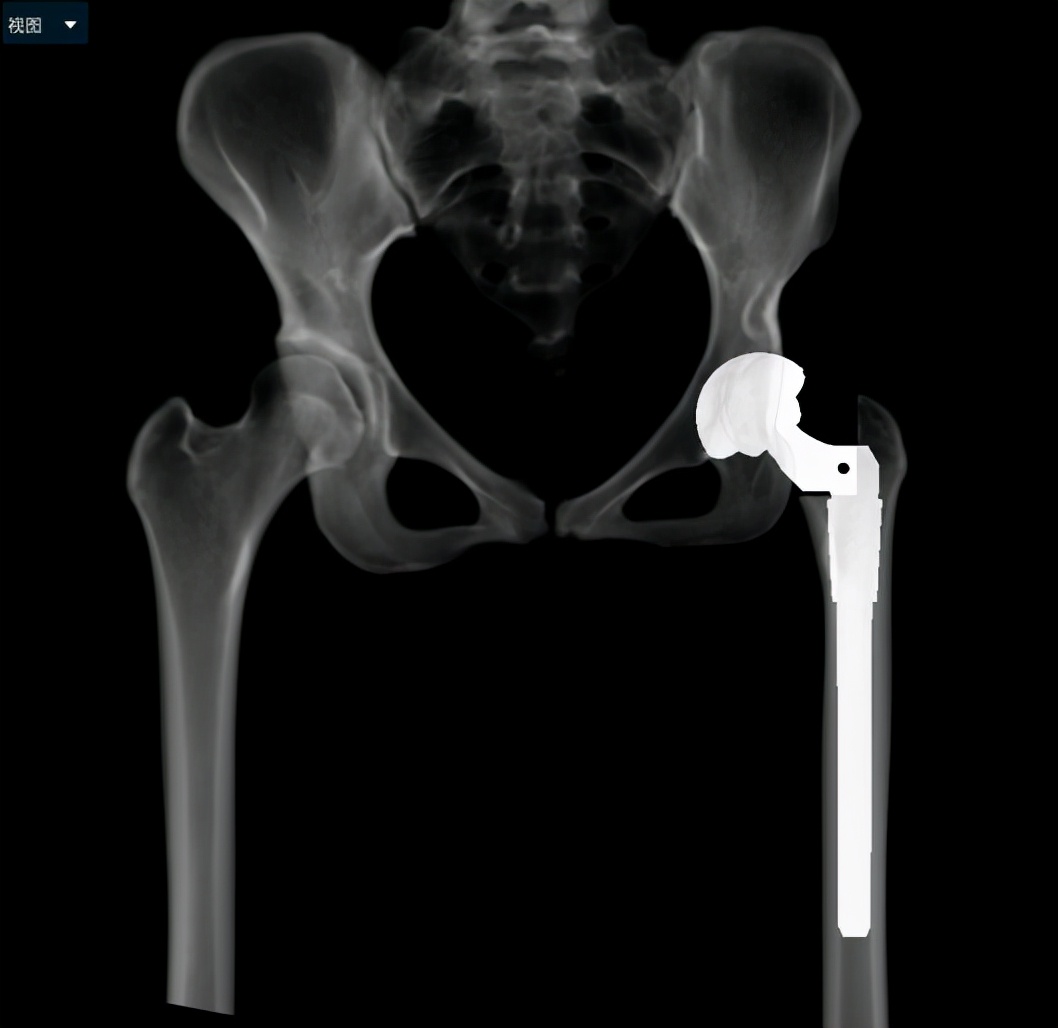

小张入院后,立即开始逐步进行相关检查,进行术前的准备。因为DDH的手术一般比较复杂,特别是这种脱位程度较高的患者,所以术前就需要更加精准的规划。对于小张的手术方法,耿硕副教授制定了两套方案:1.如果原来真臼内及股骨头的软骨条件良好并且相匹配的话,那么可以尝试将股骨头放进髋臼里配合骨盆截骨重建髋关节;2.如果软骨条件不好或难以匹配,那么只能行全髋关节置换术。但是所有手术方案都会有一个挑战,就是如果在安装完髋臼杯及股骨假体后复位时把股骨下拉过多,可能会造成神经等软组织的牵拉伤并且且因软组织张力过大可能造成假体松动,为了避免这种情况可能需要行股骨截骨减张,这样一期便不能恢复双下肢等长,需二期行骨延长术恢复下肢等长。在术前,为了适应软组织的张力状态及验证复位可能性,小张入院后即进行了患肢的牵引处置。为了精准的对手术做出规划,术前小张进行了下肢全长的三维CT扫描和模型重建,并且应用人工智能系统AI HIP对其进行术前手术方案的制定。人工智能能够利用患者的三维CT数据进行智能化识别解剖位点,匹配假体的大小及安放位置,通过对手术精准地预演,让外科医生在术前心中有数。通过人工智能系统的规划,计算出小张同学的双下肢腿长差和偏距差,计算出了旋转中心所需下移的距离和假体需要安放的位置等,髋关节置换方案为S-ROM假体系统,髋臼杯为PINNACLE 44号,内衬为BIOLOX28-44,因为患者比较年轻,所以选用了陶瓷对陶瓷的摩擦界面,能够实现更长的使用年限。根据术前规划数据,毕郑刚、耿硕团队提前准备了相应的假体和器械,为手术做了充分的准备。

人工智能术前规划